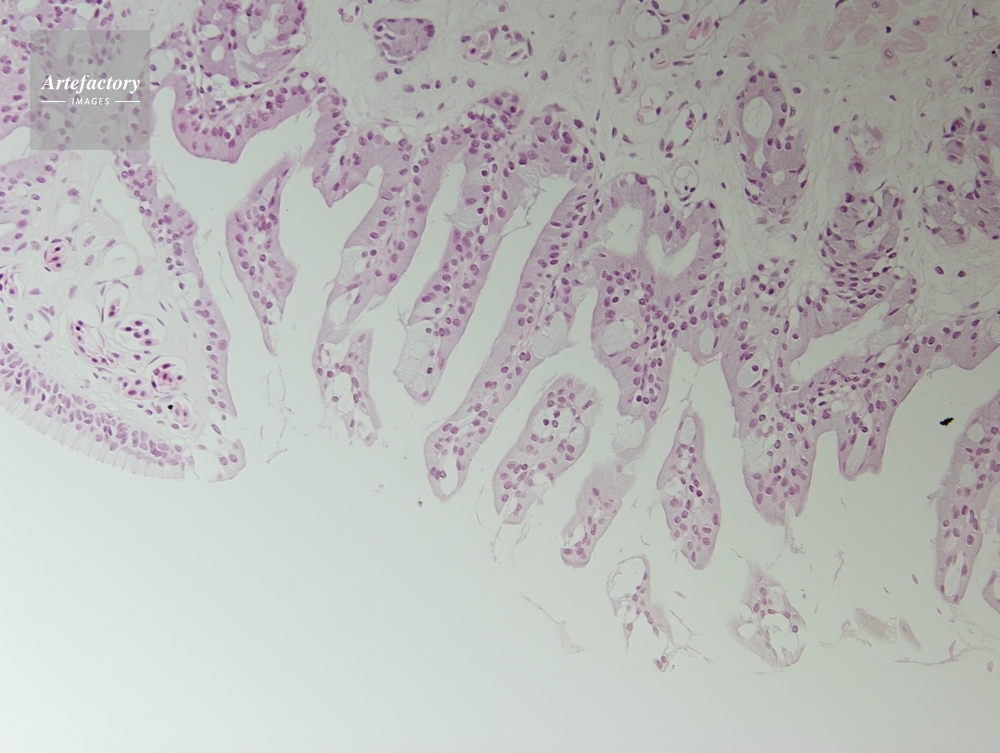

| 作品タイトル | カエル,舌 | モデルリリース | なし | |

| 作家 | OLYMPUS CORPORATION Technolab | プロパティリリース | なし | |